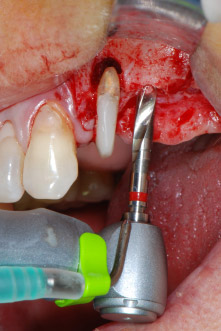

Въпреки това, ние се придържахме към първоначалния си план да запазим и двата зъба като абатмънти за временен мост по време на 6-месечната остеоинтеграция на имплантите. При повторна интервенция, ситуацията трябва да се преразгледа. Първо, в опит да се овладее ендо-перио проблема, останалата повърхност на зъба е внимателно обработена с пиезохирургично оборудване (Piezomed, W&H, използван с накрайник S1 под формата на шпатула, първоначално проектиран за ерозия на латералната синусна стена) (Фиг. 4).

Имплантологичното ложе е подготвено в позиции 25 и 26 с ротиращи инструменти, използвайки обратен наконечник 20:1 с усъвършенстван и мощен имплантологичен мотор (Implantmed, W&H) (Фиг. 8).